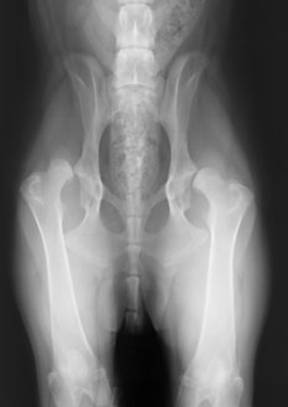

HD freies Gelenk

Hochgradige HD